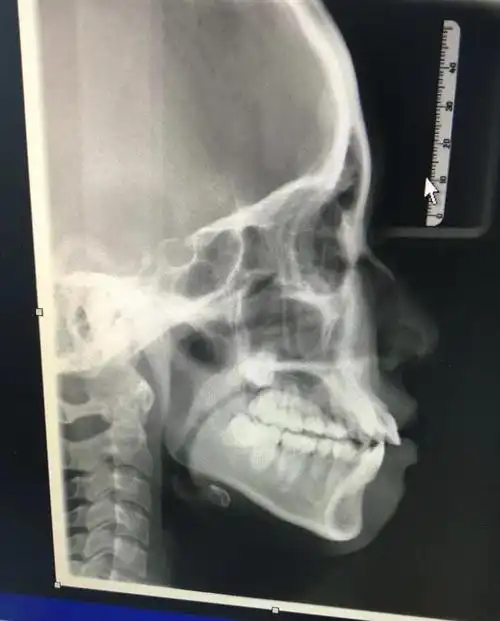

初诊时无论是侧貌,x光片都存在前突,牙齿唇倾的问题

牙片八个月的侧脸差距

由正畸医师进行临床资料的采集,拍口腔全景x光片,还有面部,牙齿和口腔